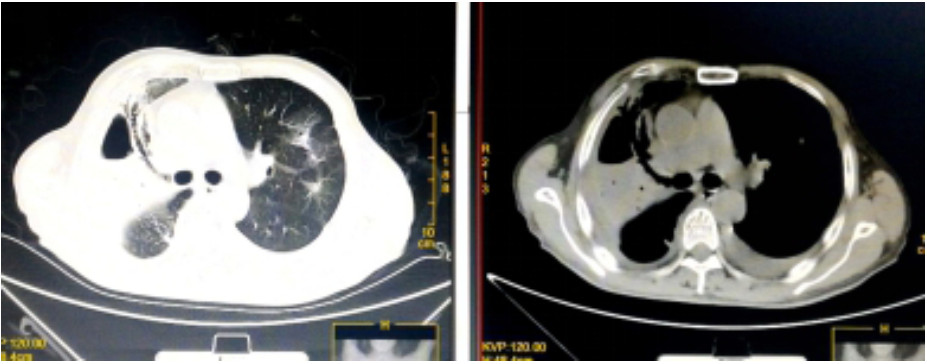

入院诊断“社区获得性肺炎”。予无创呼吸机支持(FiO2 75%),经验性予以美罗培南静脉泵入1.0 g 2次/d、磷酸奥司他韦口服75 mg 2次/d、莫西沙星静脉滴注0.4 g 1次/d。入科后治疗4 h仍无尿,且呼吸困难进行性加重,血氧饱和度进行性下降,氧合指数109 mmHg,予以经口气管插管接呼吸机辅助通气及连续性血液净化等治疗。机械通气后,吸出大量灰褐色痰,且病情进展快,短时间无法脱机拔管,12月17日气管切开。12月17日复查血常规:血白细胞2.49×109/L,中性粒细胞百分比0.925,血红蛋白70 g/L,血小板62×109/L。停用莫西沙星改用利奈唑胺0.6 g静脉滴注2次/d。12月19日胸部CT示,⑴双肺散在多发感染性病变,右侧为著;⑵右肺空腔伴气液平;⑶右侧胸腔积液(图 2)。12月19日血白细胞3.7×109/L,中性粒细胞百分比0.882,淋巴细胞百分比0.098,血红蛋白78 g/L,血小板115×109/L,入科后立即送检的血、痰培养回报均阴性。12月20日肺泡灌洗液病理回报镜下见炎症细胞、吞噬细胞及菌丝样物,未发现恶性细胞(图 3)。12月21日痰宏基因组学检测回报:肺炎链球菌(序列数113 916)、屎肠球菌(序列数1 307)、铜绿假单胞菌(序列数16)。12月20日及24日肺泡灌洗液、血培养均回报为屎肠球菌,药敏试验结果示,对氨苄青霉素、环丙沙星、红霉素、庆大霉素、青霉素耐药;对替考拉宁、替加环素、利奈唑胺、万古霉素、奎奴普丁/达福普丁敏感。继续利奈唑胺600 mg 2次/d,总疗程62 d。治疗期间血红蛋白在66~91 g/L,血小板均在(100~300)×109/L。12月26日CT引导下经皮肺组织穿刺术,并送检病理细胞学及组织培养,结果显示符合炎症性病变改变,病原学阴性。2020年1月9日脱离呼吸机,1月14日转入普通病房,1月23日拔出气管切开套管,2020年2月13日复查胸部CT病灶有所吸收(图 4),2月24日好转出院。出院半年后电话随访,当地医院复查胸部CT示病灶较前明显吸收,已经正常工作。

| 图 4 2020年2月13日胸部CT结果(双肺多发异常密度,右侧为著伴右肺空洞,较前有所吸收;双侧胸腔积液,右侧较前有所减少,左侧较前稍有增多) |